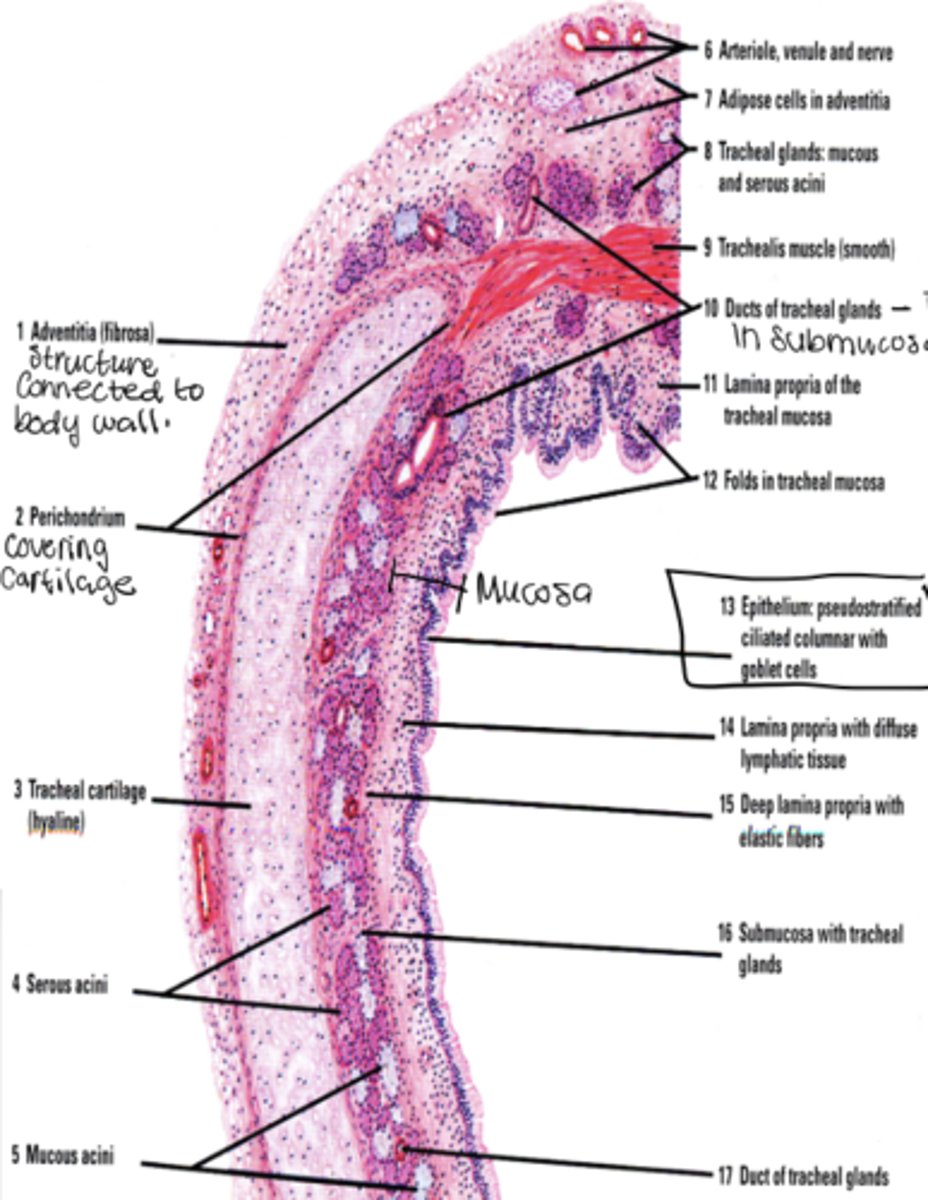

What layers make up the trachea?

Mucosa, submucosa, cartilaginous layer, adventitia.

What cell types are found in tracheal epithelium?

Goblet, basal, brush, small granule, and ciliated columnar cells.

What is another name for mucus cells?

Goblet cells.

Where are goblet cells located?

Between ciliated cells and extending from basal lamina to apex.

Why does the basement membrane appear thick and glossy?

Densely packed collagen fibers below basal lamina.

What is characteristic of the lamina propria in the trachea?

Very cellular loose CT with BALT.

What does the submucosa contain?

Dense irregular CT and glandular elements.

What type of cartilage supports the trachea?

Hyaline cartilage (16-20 C shaped rings)

Why are the cartilage rings open posteriorly?

To allow flexibility next to the esophagus.

What completes the posterior gap of the cartilage ring?

Fibroelastic membrane with trachealis muscle.

What is the adventitia?

Connective tissue layer deep to cartilage

What does the adventitia contain?

Large blood vessels and lymphatic tissue.